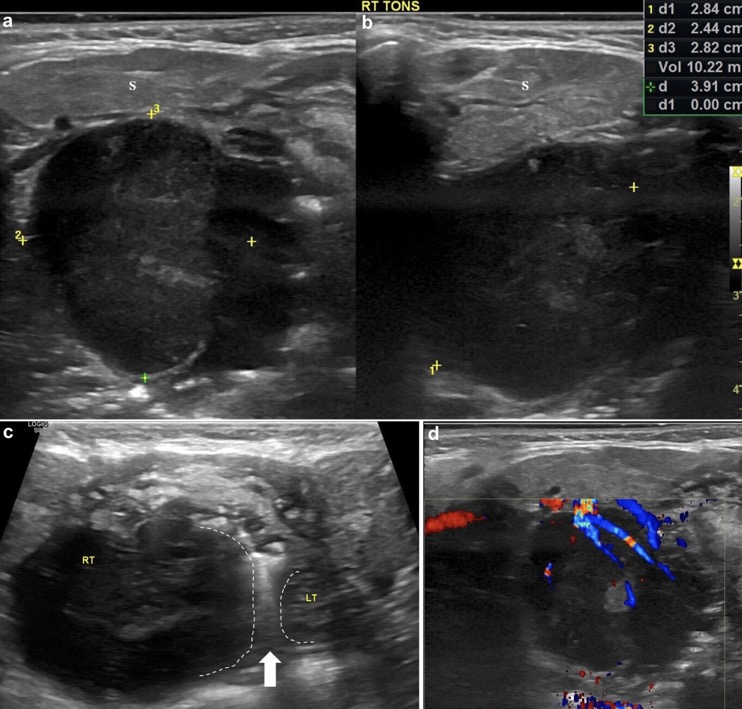

EX: LYMPHOME DE BURKITT

Résultats échographiques indiquant une malignité des amygdales

1. Asymétrie de la taille des amygdales (élargissement unilatéral)

2. Sphérique au lieu d'ovoïde

3. Altération de l'échotexture des amygdales

(A) Homogènement hypoéchogène

(B) Perte de son apparence striée

4. Augmentation de la vascularisation amygdalienne interne

5. Capsule amygdalienne bien définie mais sans limites lobulées régulières